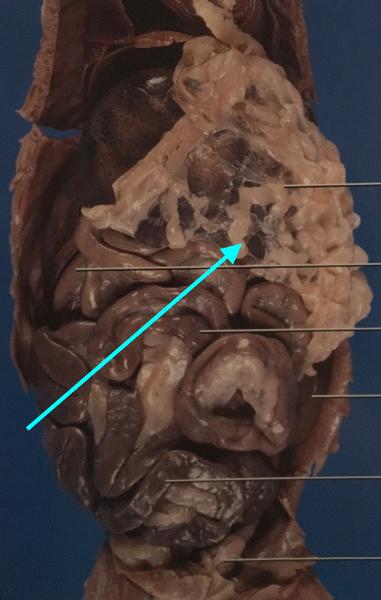

14

small intestine

- duodenum (1)

- jejunum (2)

- ileum (3)